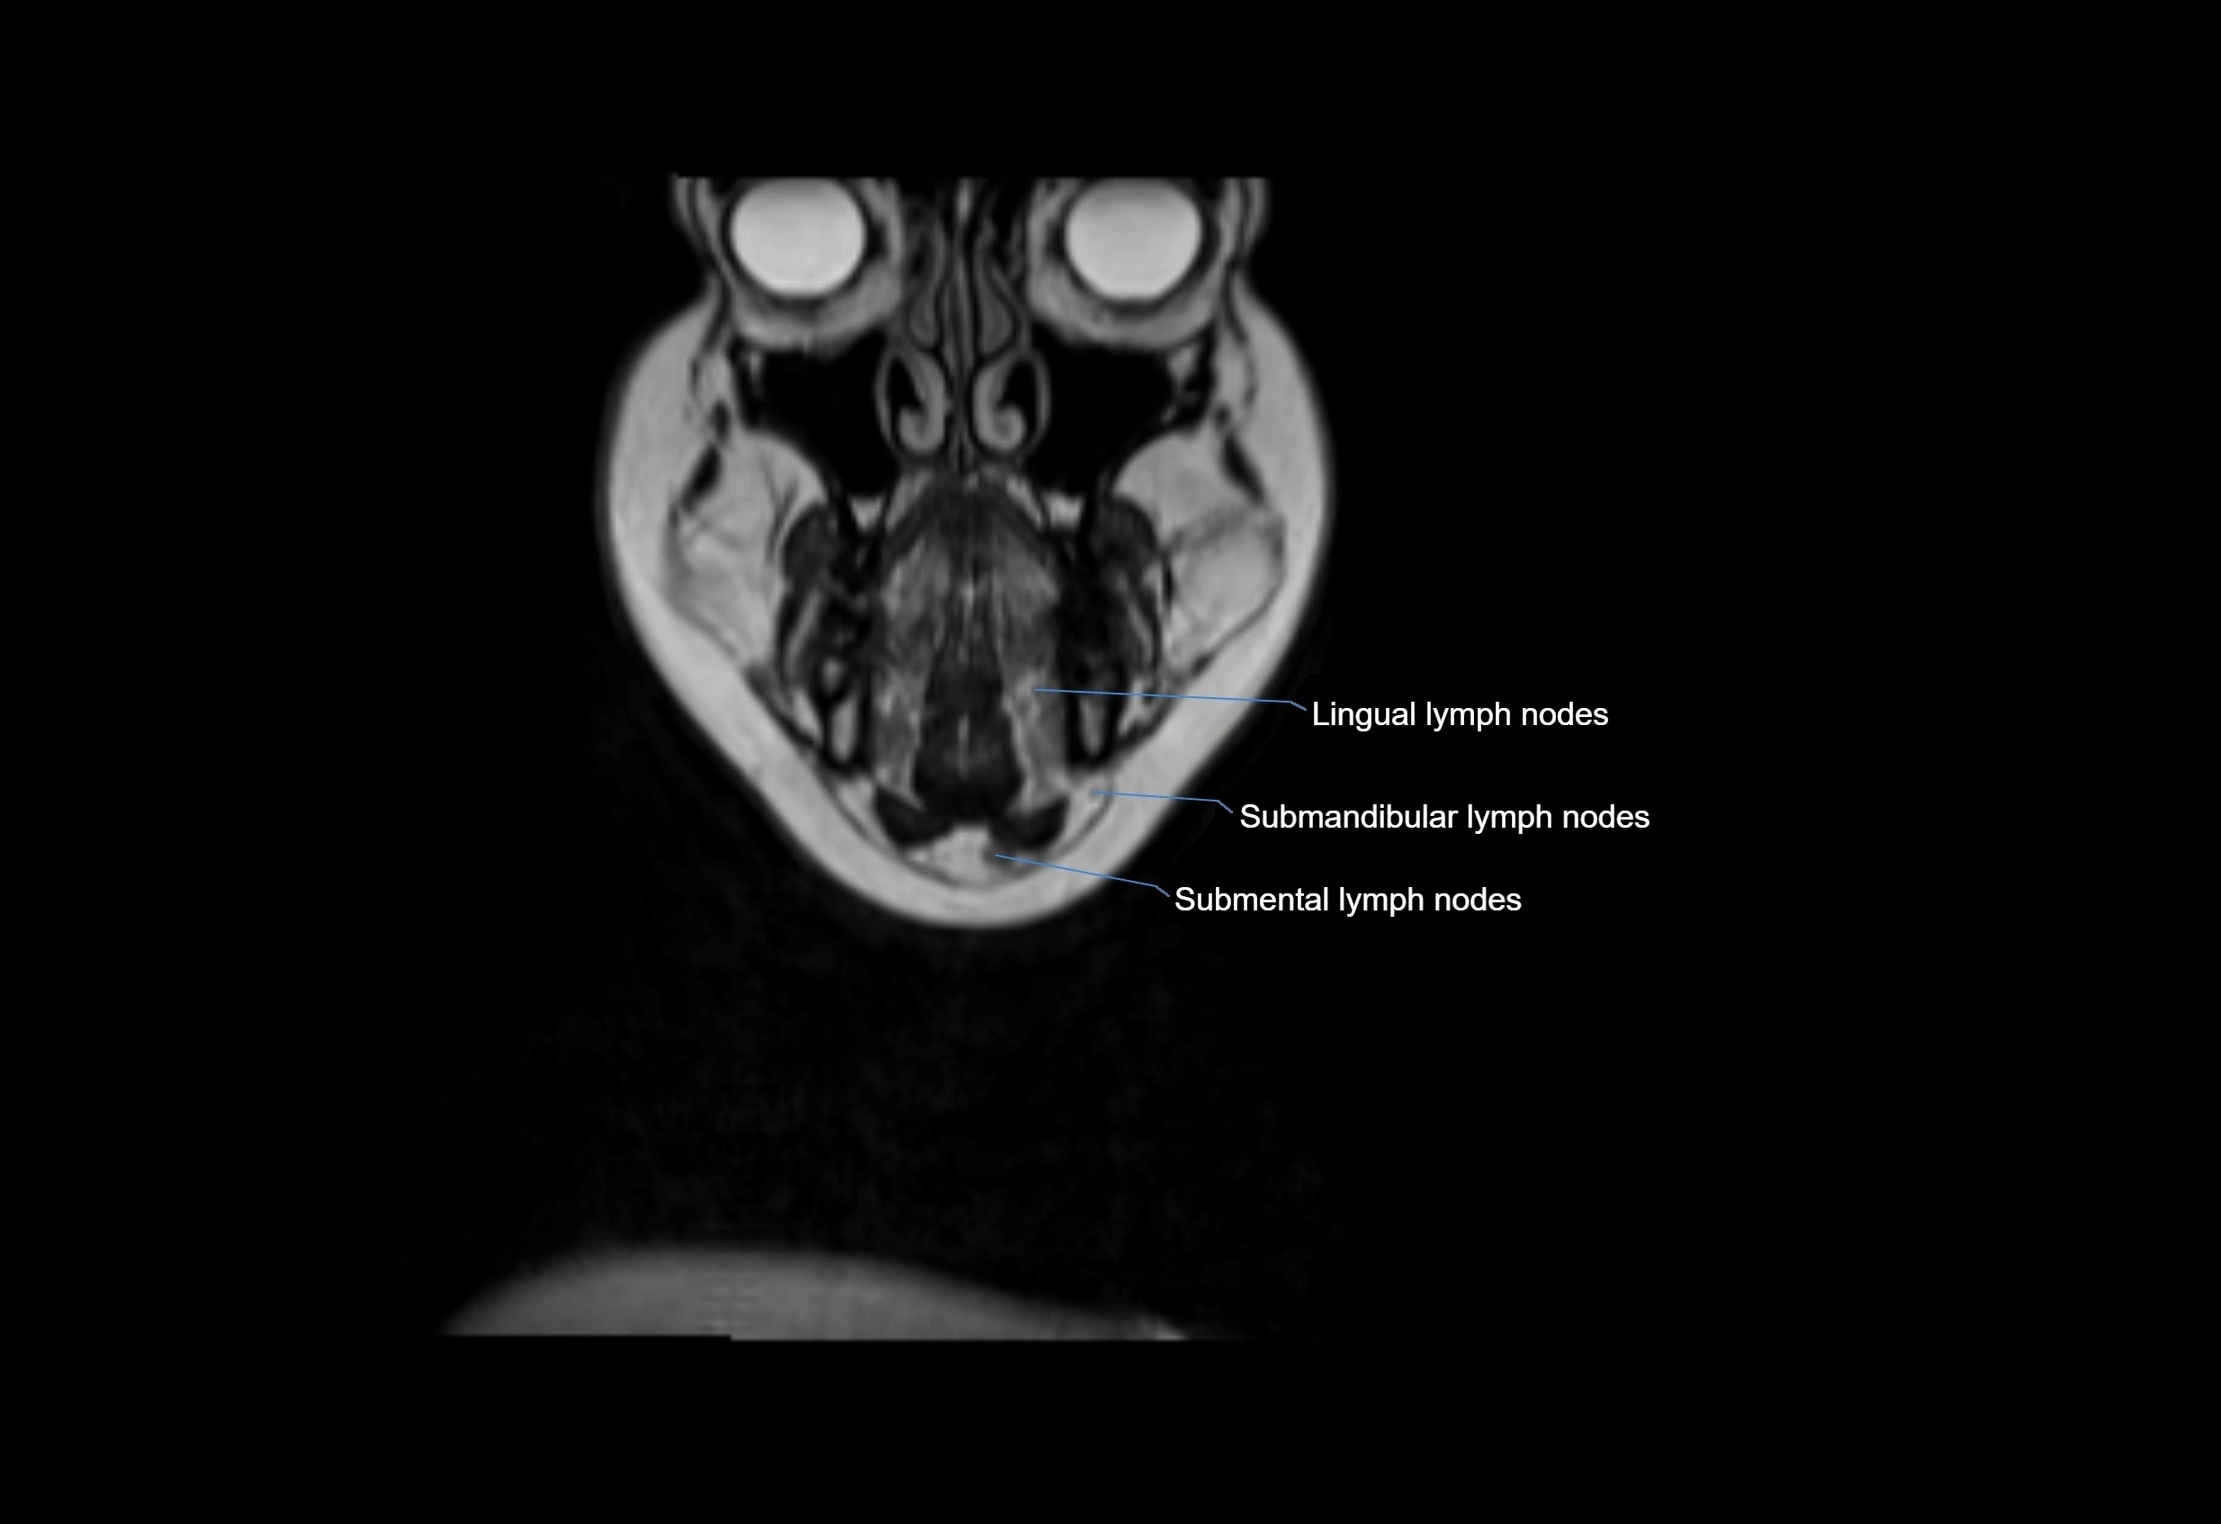

Location

• Found along primary lymph node chains, including preauricular, submandibular, parotid, and occipital regions

• Embedded in subcutaneous fat or superficial fascia, often lateral or posterior to primary nodes

MRI images

image